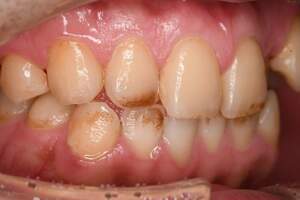

歯石除去

治療前

治療後

| 年齢 | 36歳・男性 |

| 主訴 | 歯石をとりたい |

| 治療内容 | 歯石除去 |

| 治療期間 | 30分 |

| 費用 | 約2,000円 |

| リスク・副作用 | ・歯ぐきの炎症が強いと歯石を取る際に出血することがあります。 ・処置後に歯がしみることがあります。 ・歯と歯の間に隙間ができるので、息が漏れ発音しにくいと感じることがあります。 ・歯ぐきの炎症が軽減すると歯ぐきが引き締まり、歯が長く見えることがあります。 |